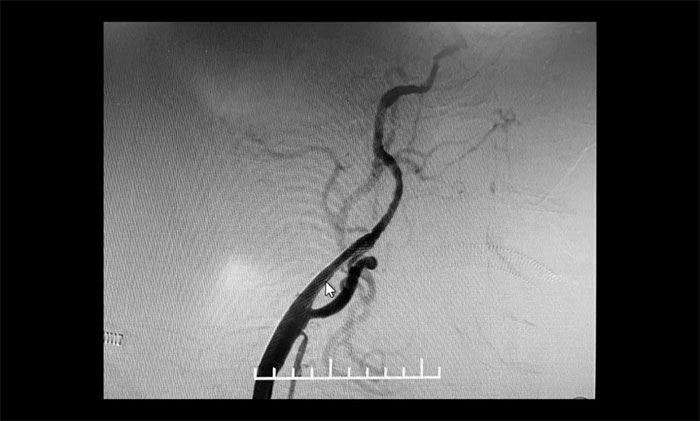

▲ 术后,左侧颈内动脉狭窄明显改善

术后康复观察一月余,于耀宇主任团队再次为曹老伯行右侧颈动脉支架置入及左侧椎动脉支架置入手术。术中造影显示,右侧颈内动脉起始段重度狭窄,狭窄长度8mm左右。左侧椎动脉 V4 段重度狭窄,长度6mm左右。运用娴熟扎实的技术,在充分做好脑保护的前提下经过多次球囊扩张后,顺利释放支架于狭窄处。造影提示支架打开良好,血管狭窄基本恢复正常,支架贴壁佳,支架内血流通畅,远端血流良好。

▲ 术后,右侧颈内动脉及左侧椎动脉狭窄明显改善